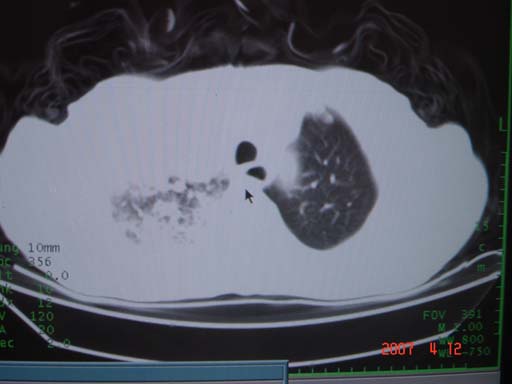

帮我 看看。男77岁咳嗽咯血2月发热2周!病人一般情况可 口痰为鲜红,有点象洗肉水(我看见他吐的痰了)

为何只有这么几幅图像?连纵隔窗都没有。但我发现上叶支气管显示不清,再加上年纪大,咯血等症状,恶性肿瘤首先得考虑。

考虑右肺新生物伴右中上肺阻塞性肺炎及含气不良,右侧胸腔积液。建议痰与纤支镜检查

考虑右侧中央型肺癌伴中上肺阻塞性肺炎、不张,胸腔积液。,建议支纤镜检查。

病灶局限在右肺中上叶,呈大片状实变影,内见空气支气管征,支气管分支较柔软,纵隔内未见肿大淋巴结.支持:感染性病变_1 大叶性肺炎.2 干酪性肺炎.

优先考虑右上肺干酪性肺炎并同侧中叶播散、胸腔积液。分析:右膈肌未见升高、纵隔未见明显右移,胸部各组淋巴结未见可疑肿大,中叶可见支气管铸形,肺野、肺门未见可确定肿块。

单从影像学上来看,该病人应首先考虑,右上肺感染(干酪性肺炎可能大)伴有右侧胸腔积液,理由如下:

1.病灶整体成宽基底征,而未见块状影

2.病灶内的透光区并不是含气支气管征,而像是坏死的肺组织后形成的

3.无肺不张的表现

4.纵隔那未见明显肿大淋巴结

右肺上叶后段支气管中断,首先考虑中央型肺癌并右肺不张及纵隔淋巴结转移,右侧胸腔积液。

右肺中心型肺癌可见支气管呈鼠尾状

有点象洗肉水的痰,其来源应当是实变引起的血细胞渗出导致,可见支气管气象,实变区有虫蚀状空洞,有明显胸腔积液,未见明显肺门区肿块影,考虑继发型肺结核,干酪性肺炎

右肺上叶实变,实变范围如此之大,如果用肺癌解释的化,应该是比较大的支气管开口发生完全阻塞,但观察上叶前后段支气管还是比较通畅,所以应考虑感染性病变,大叶性肺炎可能,建议抗炎治疗后复查。